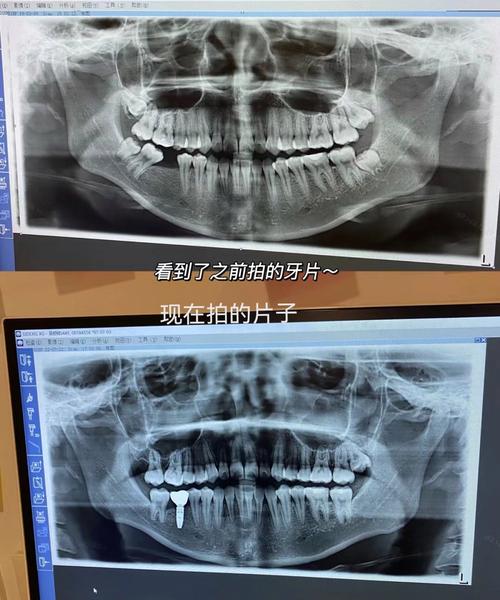

- 全景片(曲面断层片):可全面展示全口牙齿的形态、数量、位置(如埋伏牙、多生牙),牙根长度、弯曲度,以及牙槽骨高度、密度,帮助判断是否存在牙根吸收、骨缺损等问题。